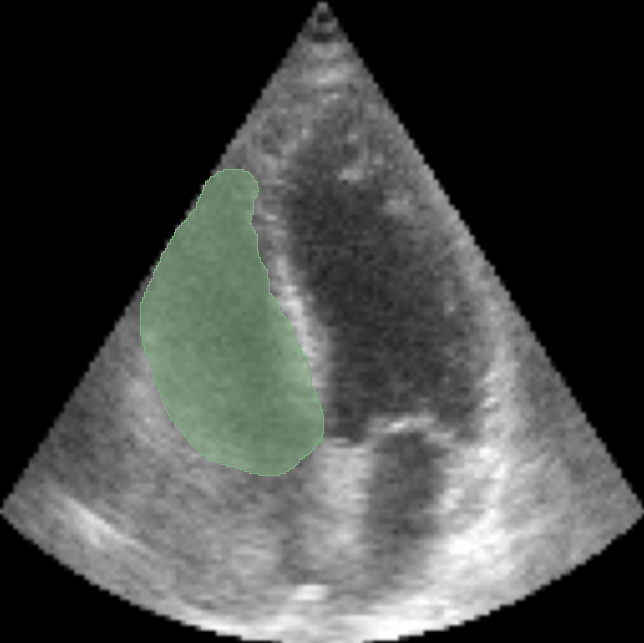

In our experimental setup, both the original and the artificially generated echocardiograms were manually annotated to obtain segmentation masks. This process allowed for precise comparison of RV volumes, assessing the efficacy and accuracy of GAN-based outpainting in reproducing anatomically coherent extensions of the cardiac structures. By comparison of the RV volumes derived from the conventional and outpainted echocardiograms, this experiment aims to validate the potential of echoGANs in overcoming the intrinsic limitations of current echocardiography practices. Comparison of segmentation for RV on original and on outpainted image is in Fig. 5 and Fig. 5.

Refer to caption

Figure 4: Segmentation over Right Ventricle for GT 4CH view with

Figure 5: Segmentation of outpainted RV with 80 degrees cut for the same 4CH view